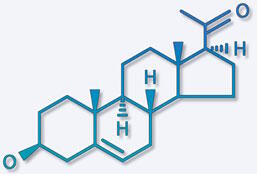

La prégnénolone La prégnénolone, abondante dans le corps humain, est formée à partir du cholestérol. Peu de choses sont connues sur le mécanisme d'action de la prégnénolone, mais elle est un élément clef du monde hormonal : elle est la molécule qui donne naissance à toutes les autres hormones stéroïdes, tels la progestérone, la testostérone, l'œstradiol, le cortisol et bien d'autres encore. |

La prégnénolone est donc transformée par des réactions chimiques grâce à des enzymes pour donner ces dérivés hormonaux. Elle est à son niveau le plus élevé entre 16 et 17 ans, puis chute fortement, pour atteindre son niveau le plus bas vers 37 ans. |